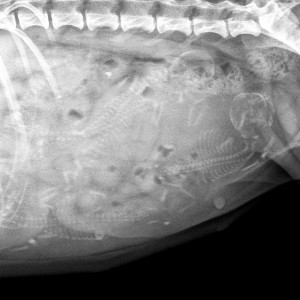

22.3. Dnes jsem jela Tessinku vyfotit. Fotky má krásné a v bříšku se jí mele celkem 5 malých pejsků

20.2. Tak konečně je jasno. Sice jsem už před 4 dny hmatala v bříšku maličké balonky, ale dnes jsem se stavila v práci a udělala Tessince sono. Není úplně spolupracující pacient, takže o pečlivém vyšetření a počítání miminek nemohlo být ani řeči, ale minimálně 4 kuličky jsem viděla spolehlivě.